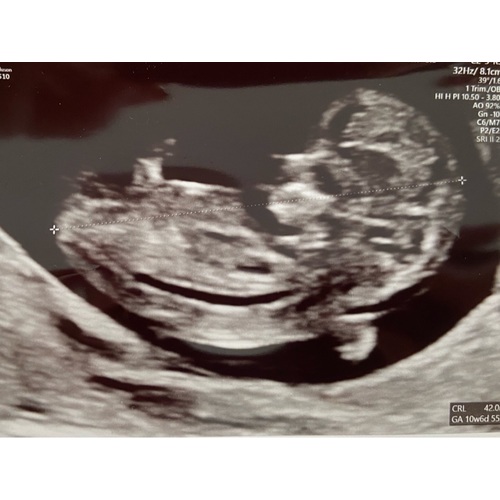

Dit was vrijdag met 10.6. Heel leuk om de armpjes en beentjes te zien bewegen. En echt uitgebreide echo gehad, hebben de doorsnede van de hersenen gezien (dan zie je een soort vlinder) en de maag en blaas (gewoon een zwarte stip 😂). Echt bizar wat er allemaal al in zo’n klein frummeltje zit!